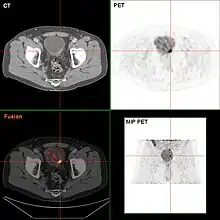

If invasive or high grade (includes carcinoma in situ) cancer is detected on TURBT, an MRI and/or CT scan of the abdomen and pelvis or urogram and CT chest or x-ray chest should be conducted for disease staging and to look for cancer spread (metastasis). Increase in alkaline phosphatase levels without evidence of liver disease should be evaluated for bone metastasis by a bone scan.[1] Although 18F-fluorodeoxyglucose (FDG)-positron emission tomography (PET)/CT has been explored as a viable method for staging, there is no consensus to support its role in routine clinical evaluations.[54]